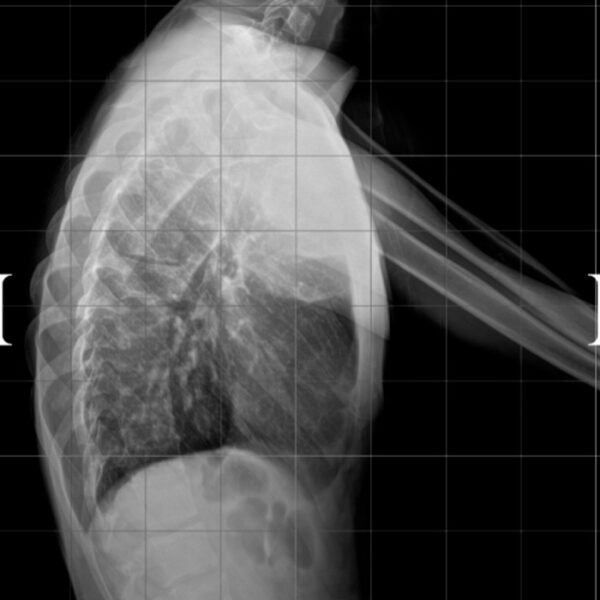

DIAGNOSI:

IPERCIFOSI DORSALE GRAVE

Radiografia dorsale pre operatoria

Intervento chirurgico eseguito:

STABILIZZAZIONE DORSO – LOMBARE CON OSTEOTOMIE CORRETTIVE

Radiografia dorsale post-operatoria